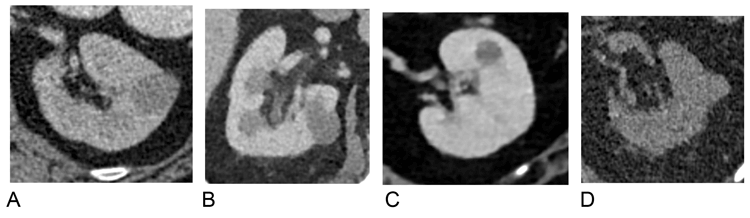

Distinct CT imaging features can allow differentiation of the various histological RCC subtypes. For instance, clear cell RCC typically appears more heterogenous and hypervascular, with a greater tendency for cystic change and tumour necrosis [9]. Papillary RCC (PRCC) appears more hyperattenuating relative to renal parenchyma on unenhanced CT. PRCC also appears more homogenous with relatively reduced vascularity, therefore demonstrating lower enhancement gradients, more likely to fall within the indeterminate range (Figure 6) [9].

Figure 6: Enhancement characteristics of individual tumour subtypes.

Papillary RCC enhances the least [11].